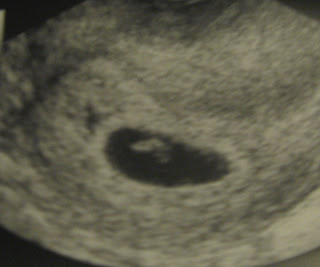

MEET HIS NEW BROTHER OR SISTER TO BE....

WE FOUND OUT LAST WEEK AND COULDN'T BE MORE EXCITED. AS MOST OF YOU KNOW GETTING TALAN TOOK A LITTLE HELP THANKS TO MANY MANY PRAYERS AND THE A.R.T PROGRAM HOWEVER THIS ONE THANKS BE TO GOD DID NOT. SO I GUESS YOU WOULD SAY WE WERE A LITTLE SHOCKED BUT IN A GREAT WAY!!

We had already made our appointment with the A.R.T program again but turned out we didn't need it however they still claim this one as their own so they are monitoring me and baby for the next few weeks which I am very pleased with which means not only do we get great care but we get ultrasounds each time we go which is wonderful!!! We ask for your prayers for a healthy pregnancy and look forward to keeping you up to date on how things go.